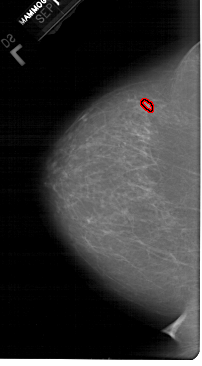

FILE: A_1549_1.LEFT_MLO.OVERLAY

TOTAL_ABNORMALITIES 1

ABNORMALITY 1

LESION_TYPE MASS SHAPE OVAL MARGINS ILL_DEFINED

ASSESSMENT 4

SUBTLETY 2

PATHOLOGY BENIGN

TOTAL_OUTLINES 1

BOUNDARY